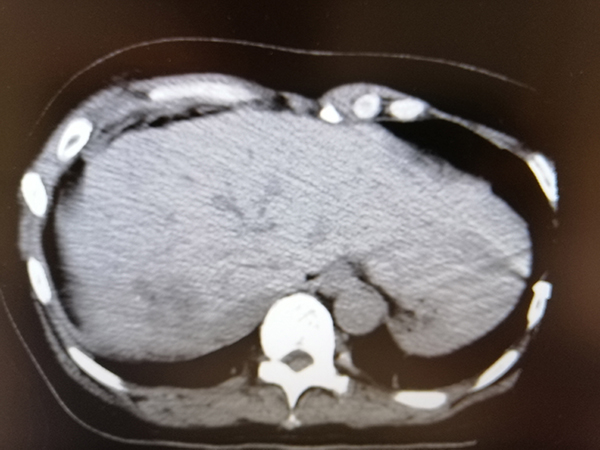

治療后